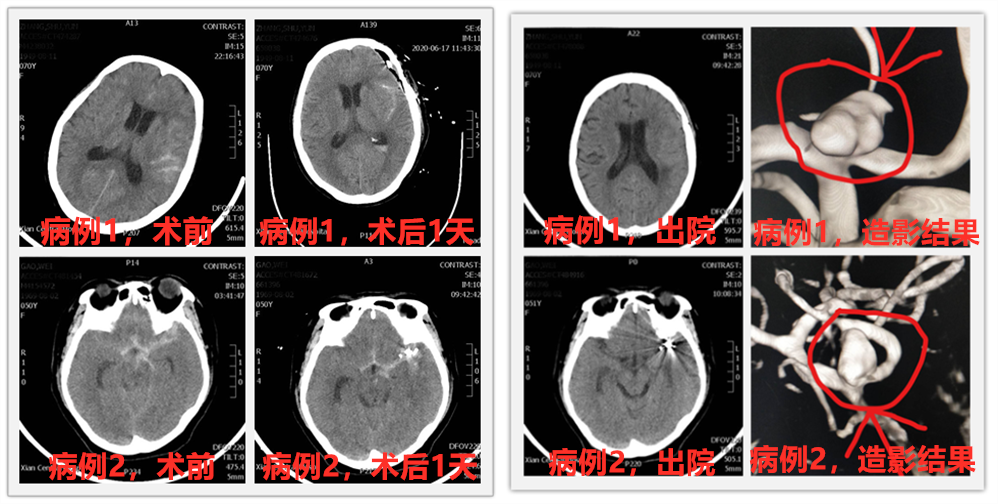

说完这么多理论,这不,六合彩生肖 神经外科最近就有两位蛛网膜下腔急性出血患者,经过脑血管造影诊断,查出分别是颅内不同血管上的动脉瘤,根据病情需要及患者家属要求,科室施展十八般武艺对付这个“坏家伙”,分别为两位患者安排了开颅动脉瘤夹闭术及颅内动脉瘤介入栓塞术,经过积极治疗,患者都康复出院,回归正常生活,获得了患者及家属的一致好评。